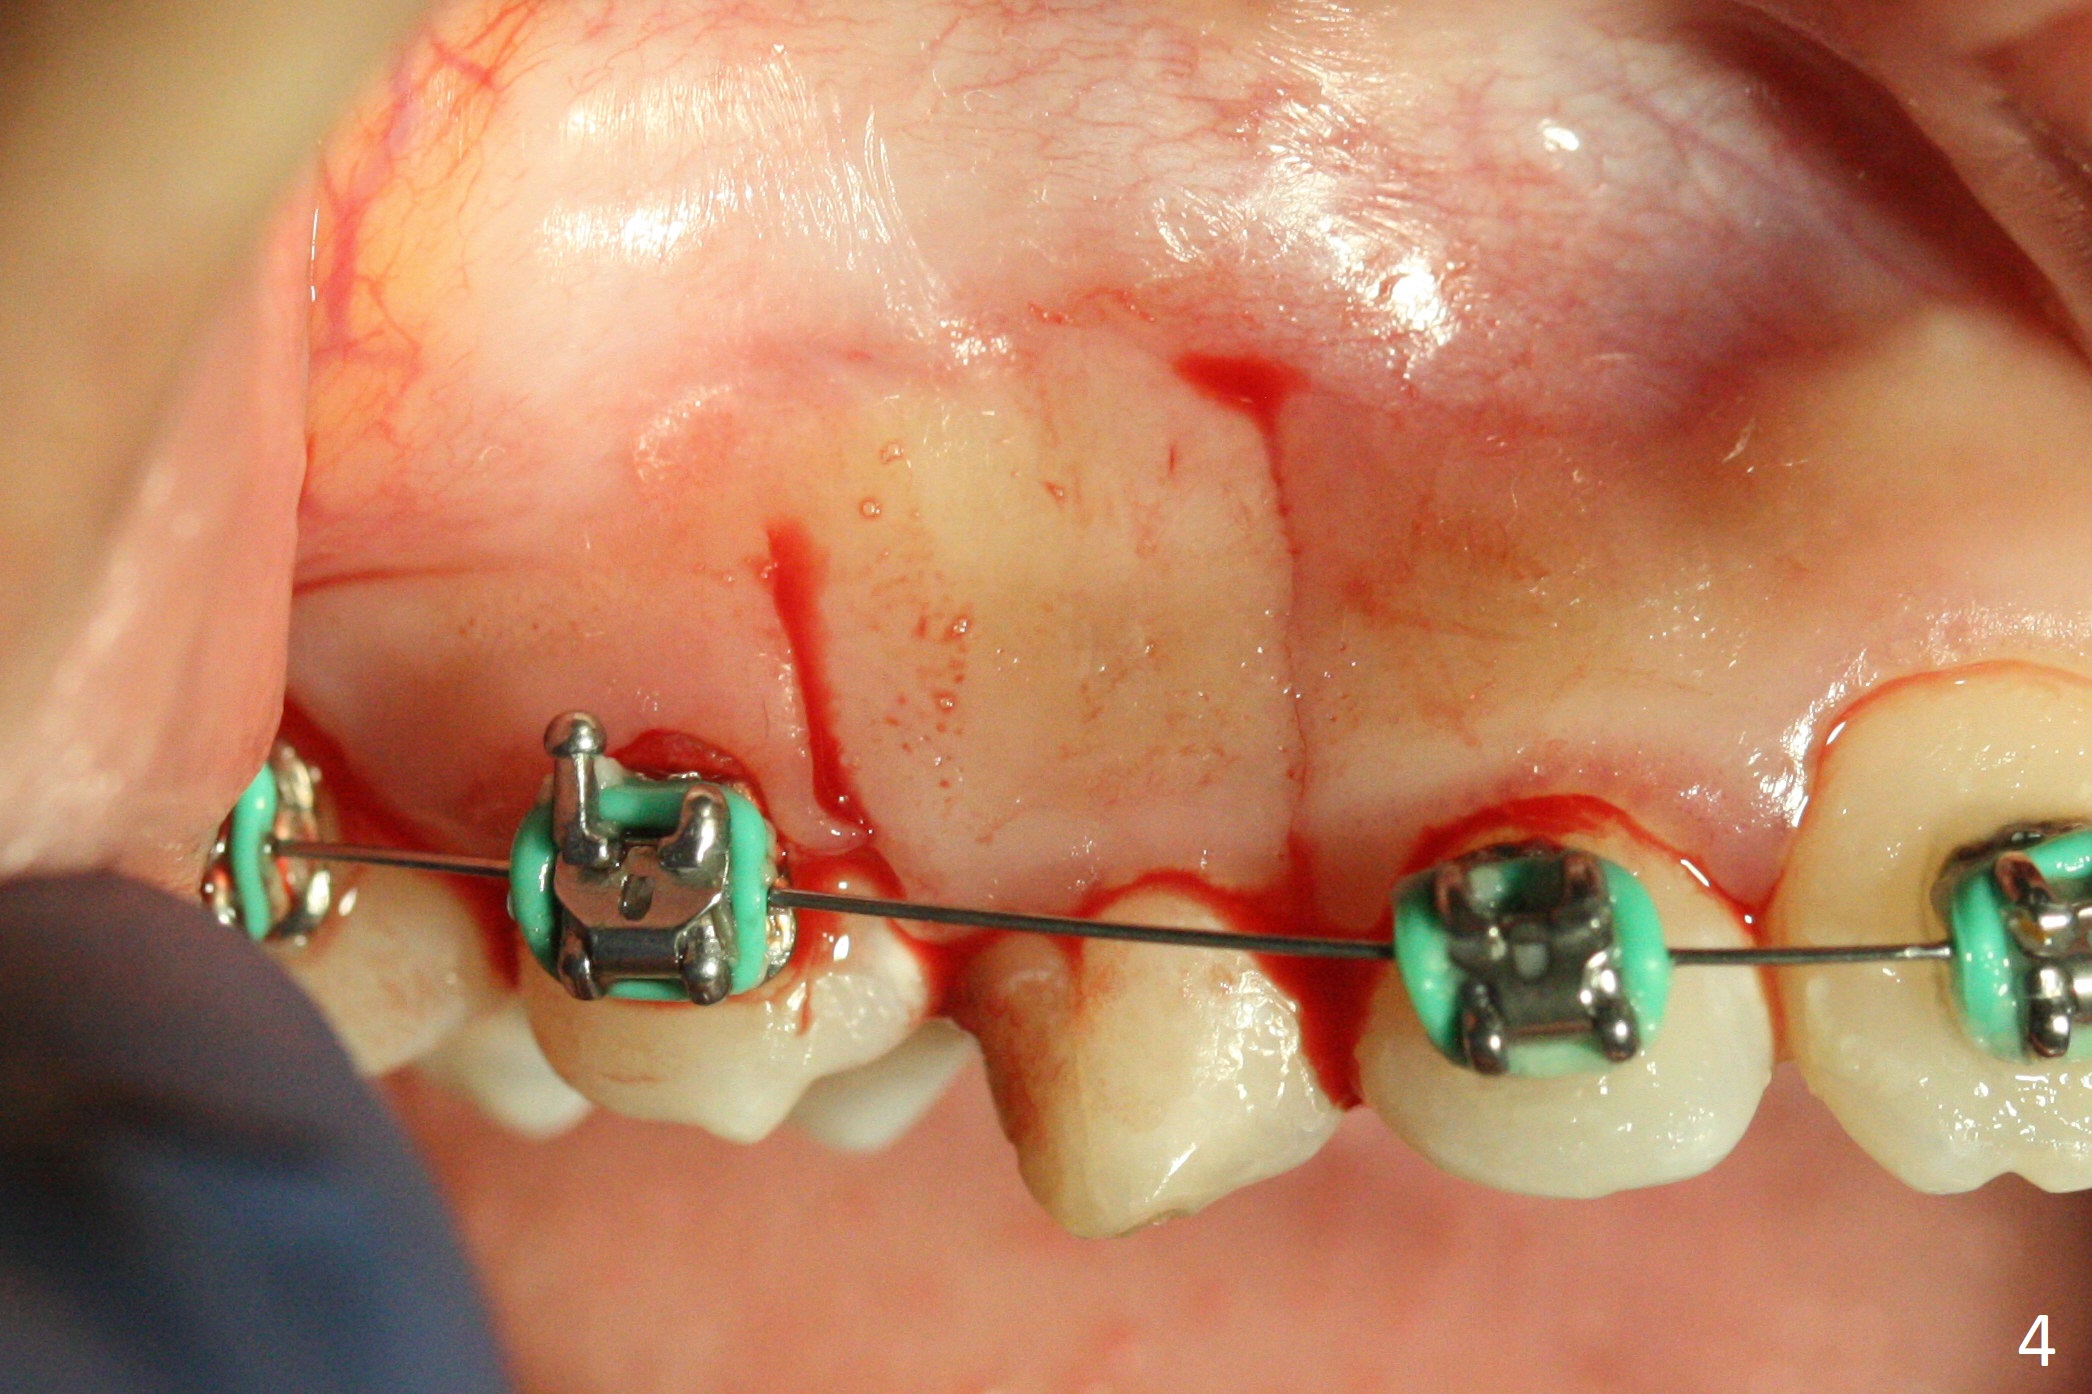

A 13-year-old woman has an impacted canine (Fig.1 (6)) and retained deciduous one (C). After initiation of orthodontics, she returns for surgical access to the impacted canine and placement of device to facilitate eruption (Fig.2,3). Incision is made buccal (Fig.4), but there is no tooth buccal (Fig.5). Extraction of the deciduous canine does not reveal the impacted one (Fig.6), but there is palatal elevation (*). Palatal access shows the impacted tooth (Fig.7) and allows placement of a retraction device (Fig.8). Careful clinical exam and CBCT are necessary diagnostic steps.